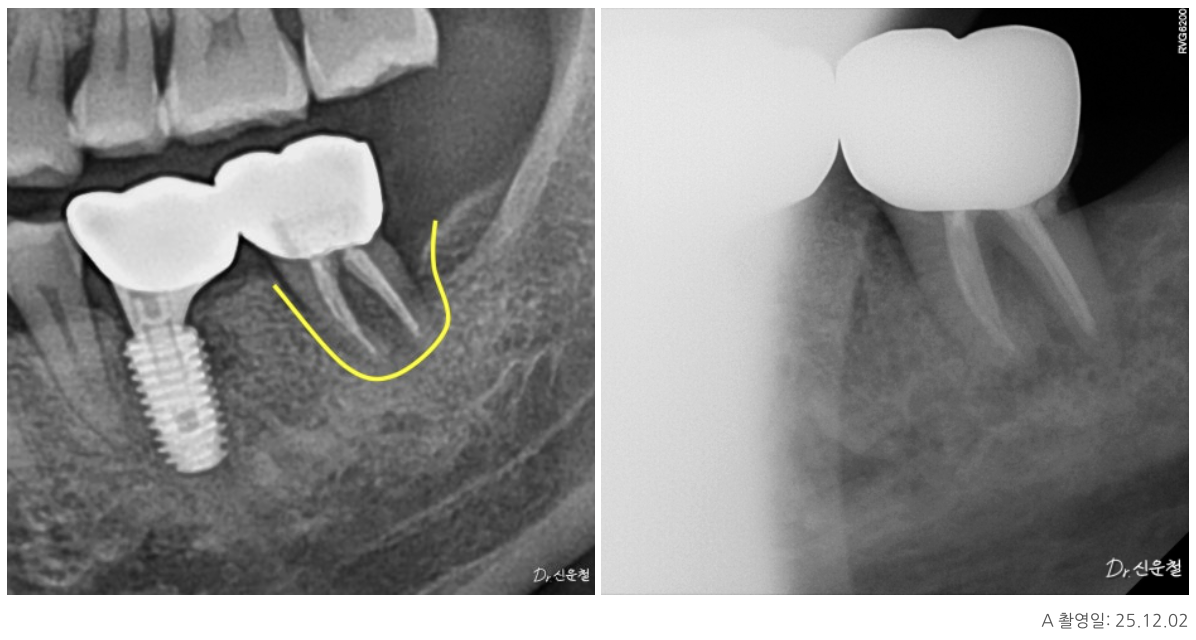

이 치아의 특징은 치아 안쪽 신경이 지나가는 길이

오랜 시간에 걸쳐 점점 막혀 있던 상태,

즉 석회화였습니다.

석회화란

원래 신경이 지나가야 할 공간이

시간이 지나면서 막히는 현상입니다.

방사선 사진에서 신경관이 잘 보이지 않거나

CT에서 신경이 있어야 할 자리가

빈 공간이 아닌 뼈처럼 보이는 경우가 이에 해당합니다.

겉으로 보면

“이제는 방법이 없는 치아”처럼 보일 수 있습니다.

치아 안쪽을 직접 확인하면서

남아 있는 길이 있는지

다시 정리가 가능한 상태인지 를 기준으로 판단했고, 그 결과

두 경우 모두 발치 대신 신경치료를 진행할 수 있었습니다.